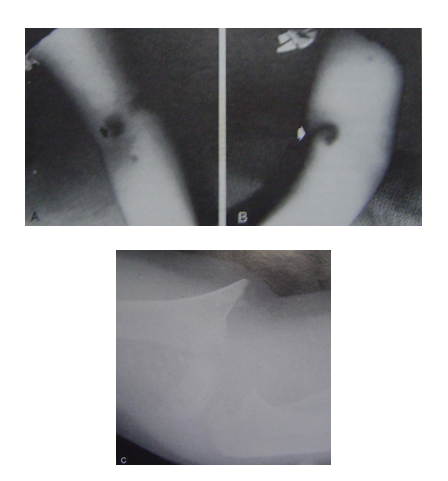

A 透视下骨折移位,拔除克氏针重新复位,三根克氏针固定

B 内侧克氏针固定方法:拇指挤压肱骨内上髁许时,水肿消退,拇指压迫下移到后方,保护尺N,穿针时有软T保护套更好

第三根克氏针内侧固定